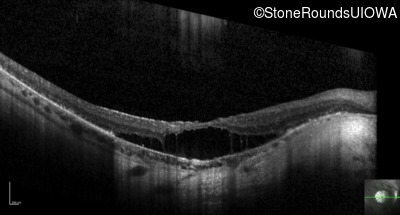

Optical Coherence Tomography - Right - 20/125 +1

Exemplar / OCT Stack

OCT Stack